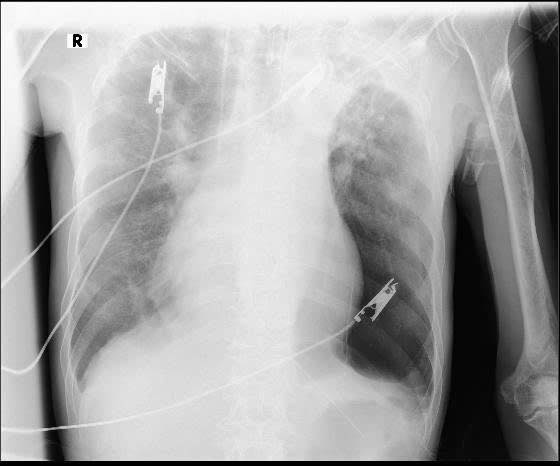

Kết quả chẩn đoán hình ảnh cho thấy tổn thương phổi hai bên rất nặng, kèm theo tràn dịch màng phổi bên phải và tràn khí màng phổi bên trái. Xét nghiệm đờm phát hiện trực khuẩn kháng cồn – kháng toan, gợi ý lao phổi đang hoạt động trên nền phổi đã bị phá hủy kéo dài. Theo ThS.BS Trương Tư Thế Bảo, đây là hậu quả điển hình của lao phổi không được điều trị triệt để, kết hợp với việc hút thuốc lá và lạm dụng rượu bia trong nhiều năm, khiến cấu trúc phổi bị tổn thương lan tỏa, khả năng trao đổi khí suy giảm nghiêm trọng và rất khó hồi phục.

Hiện bệnh nhân đang được duy trì thở máy và hồi sức tích cực. Tình trạng tạm thời ổn định nhưng tiên lượng còn rất dè dặt do tổn thương phổi hai bên nặng nề, nền thể trạng suy kiệt và bệnh lao kéo dài không được kiểm soát. “Lao phổi là bệnh hoàn toàn có thể điều trị khỏi nếu người bệnh tuân thủ đúng phác đồ. Việc bỏ thuốc giữa chừng không chỉ khiến bệnh nặng lên mà còn làm tăng nguy cơ kháng thuốc, gây tổn thương phổi không hồi phục và đe dọa trực tiếp tính mạng,” ThS.BS Trương Tư Thế Bảo nhấn mạnh.